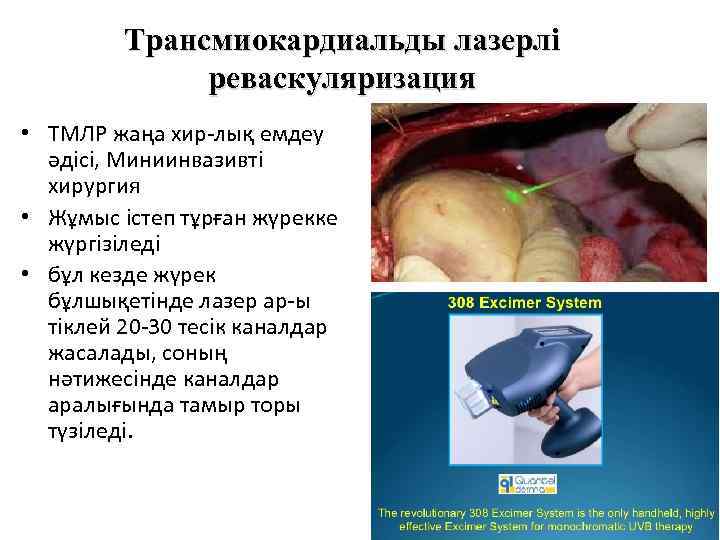

Трансмиокардиальды лазерлі реваскуляризация • ТМЛР жаңа хир-лық емдеу әдісі, Миниинвазивті хирургия • Жұмыс істеп тұрған жүрекке жүргізіледі • бұл кезде жүрек бұлшықетінде лазер ар-ы тіклей 20 -30 тесік каналдар жасалады, соның нәтижесінде каналдар аралығында тамыр торы түзіледі.

Трансмиокардиальды лазерлі реваскуляризация • ТМЛР жаңа хир-лық емдеу әдісі, Миниинвазивті хирургия • Жұмыс істеп тұрған жүрекке жүргізіледі • бұл кезде жүрек бұлшықетінде лазер ар-ы тіклей 20 -30 тесік каналдар жасалады, соның нәтижесінде каналдар аралығында тамыр торы түзіледі.